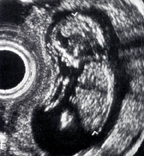

The latter problem was solved in 1998 with the hybridization of PET with CT by David W. Townsend, Ph.D, at the University of Pittsburgh and Ron Nutt, Ph.D., then president of CTI PET systems. This flung wide open the flood gates for metabolic/anatomic imaging of cancer patients in the early 2000s. The first prototype PET/CT scanner, designed and built by CTI PET Systems in Knoxville, Tenn. (now Siemens Molecular Imaging), began operating in 1998.